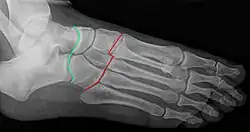

Radiographie du pied : articulation de Chopart (talo-navicualire et calcanéo-cuboïdienne) en vert, et articulations de Lisfranc (tarso-métatarsiennes) en rouge.

François Chopart est notamment connu pour avoir mis au point une technique d'amputation, longtemps appliquée sur les champs de bataille, consistant à sectionner le pied non pas à travers l'os, mais en suivant les articulations talo-naviculaire et calcanéo-cuboïdienne (qui ont d'ailleurs été regroupées sous la dénomination d'articulation de Chopart en hommage au chirurgien).